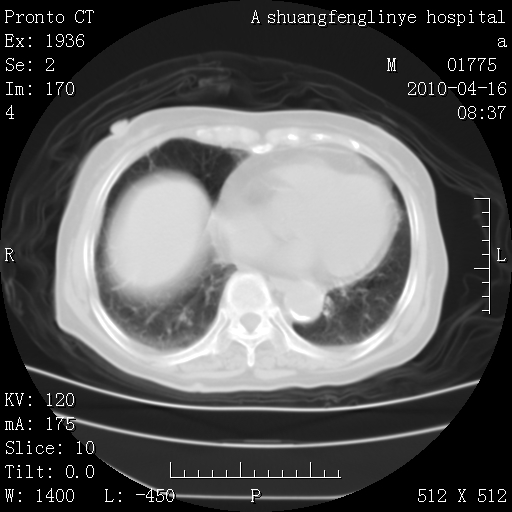

考虑左肺上叶增殖灶、纤维灶。

慢支肺气肿,左上陈旧性结核,主动脉冠脉钙化

1)左肺上叶结核(纤维、增殖病灶)。2)冠状动脉及主动脉钙化。

1)左肺上叶结核(纤维、增殖病灶)。2)冠状动脉及主动脉钙化。肺动脉高压